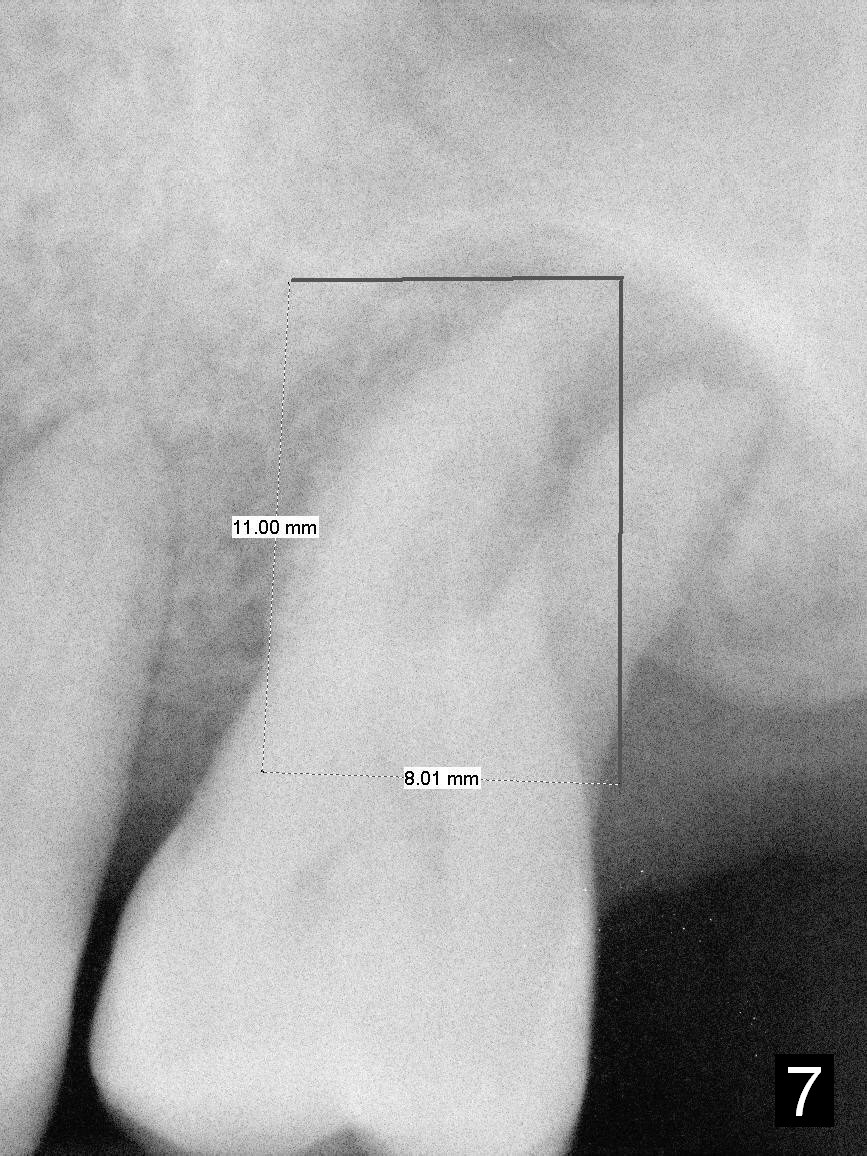

A large implant is place so that the mesiodistal dimension of the socket is obliterated by the implant (Fig.6 green circle). The buccal (Fib.5 B) and palatal gaps are filled with bone graft. It appears that either tapered (Fig4) or cylindrical (Fig.7) implant should be able to occupy the socket and obtain primary stability without perforating the sinus floor.